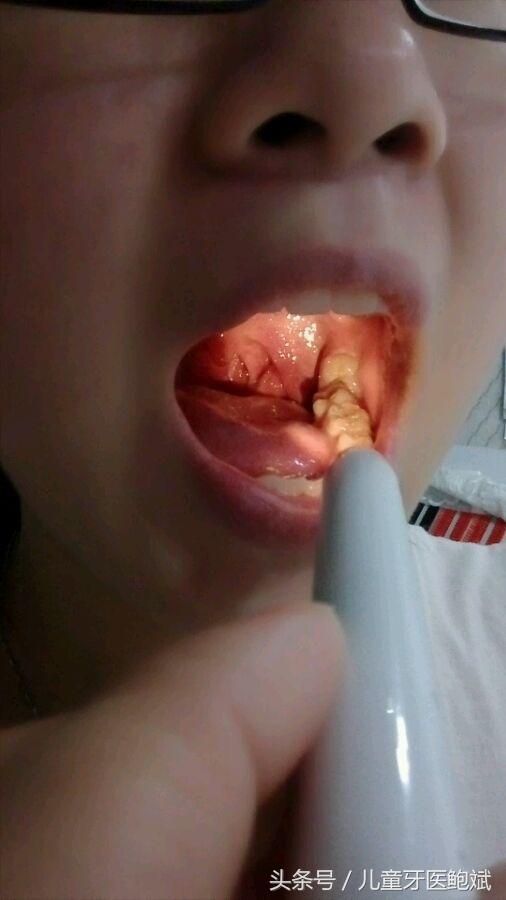

由于塞牙太常见,所以人们往往不会认为塞牙是什么大毛病,不引起重视。实际上,如果你经常塞牙,就应该去看看牙医。几乎所有的龋齿患者都发生过塞牙,其中有一种情况特别难受,就是龋齿发生两颗牙的邻接面,这里有一个龋洞,吃的东西都会塞进去。